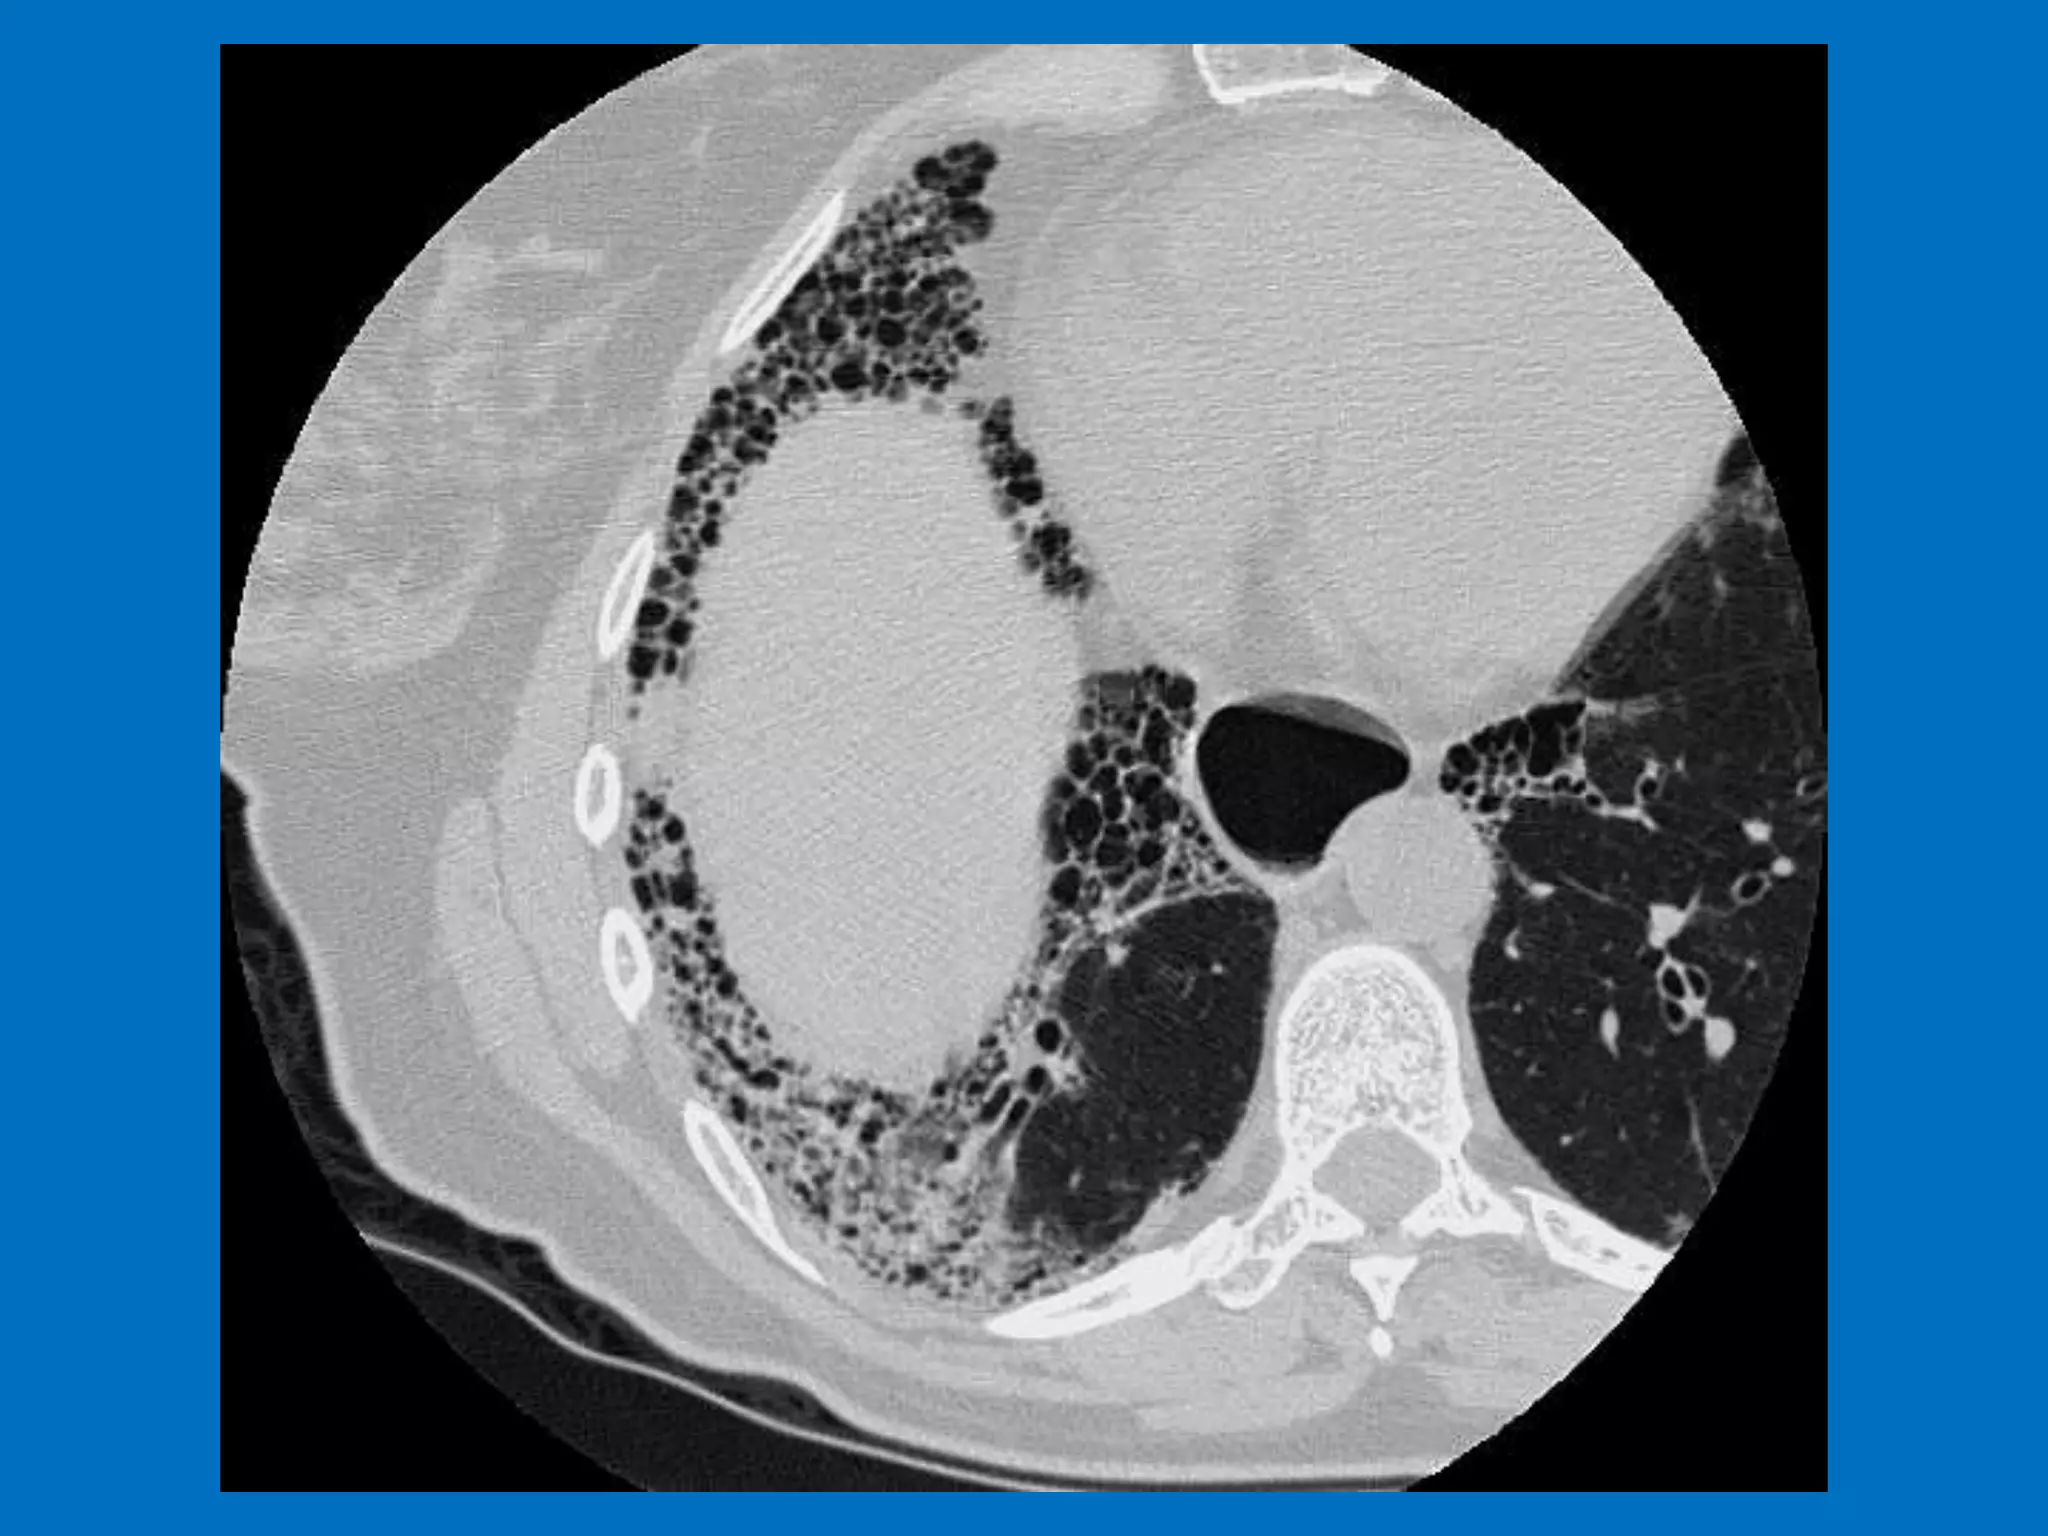

Scleroderma lung disease encompasses various respiratory complications, including interstitial fibrosis and alveolar ductitis, which are prevalent in patients. Recent research has identified differential gene expression in lung fibroblasts and new treatment options like antifibrotic and anti-inflammatory drugs. Despite the challenging prognosis, ongoing studies are promising in elucidating the disease mechanisms and potential therapeutic targets.